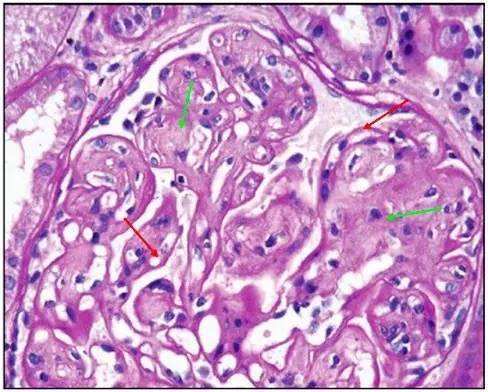

图 34 PAS 染色 绿色箭头:肾小球系膜区基质增多;红色箭头:肾小球基底膜增厚